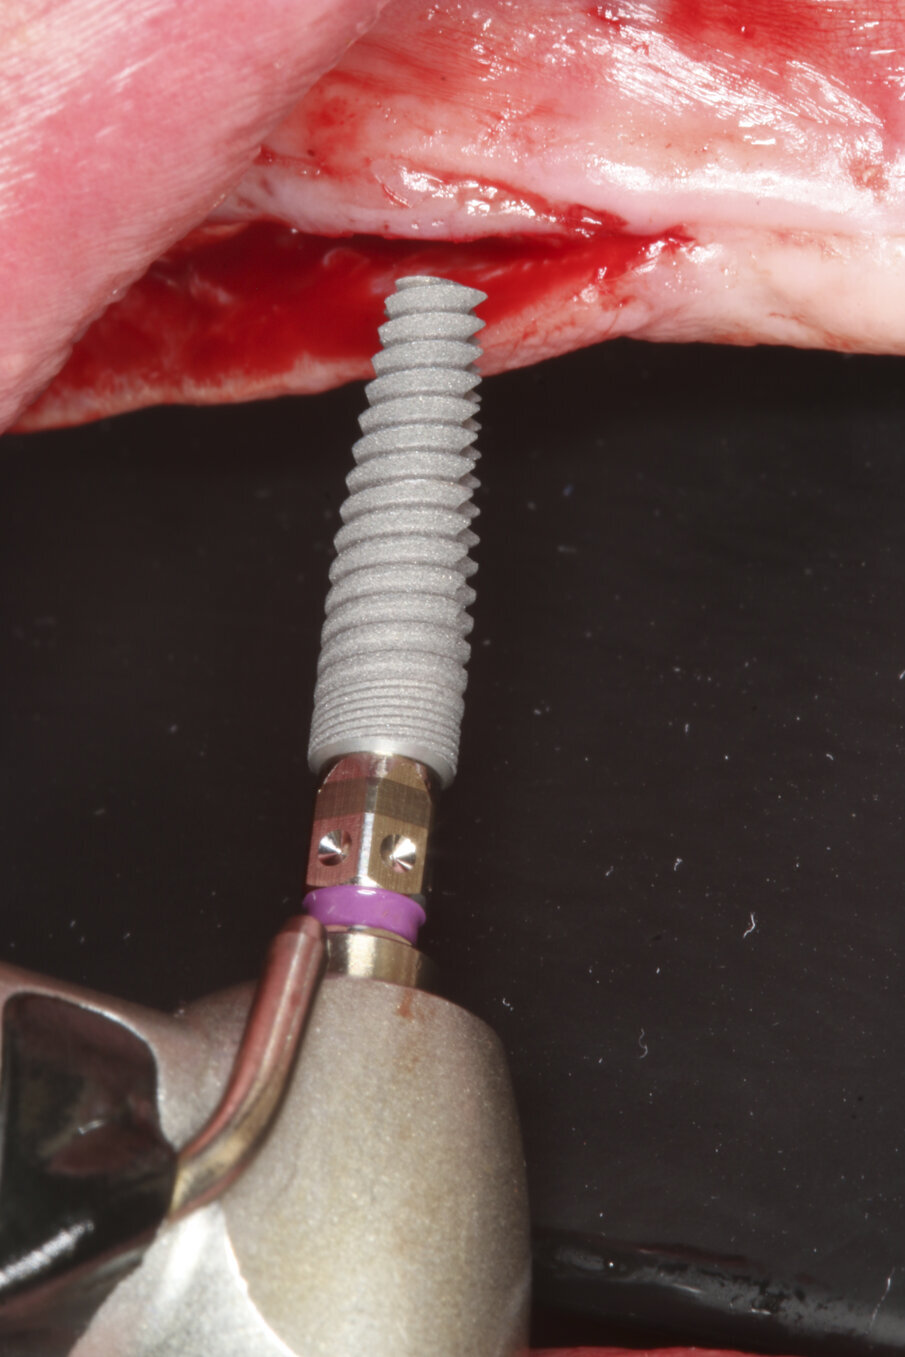

Prior to surgery, intra-oral scans of the edentulous upper jaw and dentate lower jaw were performed. The existing denture was used first as a surgical guide and then as a provisional prosthesis, after removing the palate (Fig. 4). Immediately after implant placement (Figs. 5–10), abutment position was registered with an intra-oral scan (Fig. 11). The provisional prosthesis was prepared fromthe existing denture (Figs. 12 & 13) and then the Atlantis BridgeBase was designed (Fig. 14).

Fig. 6: Implant insertion.